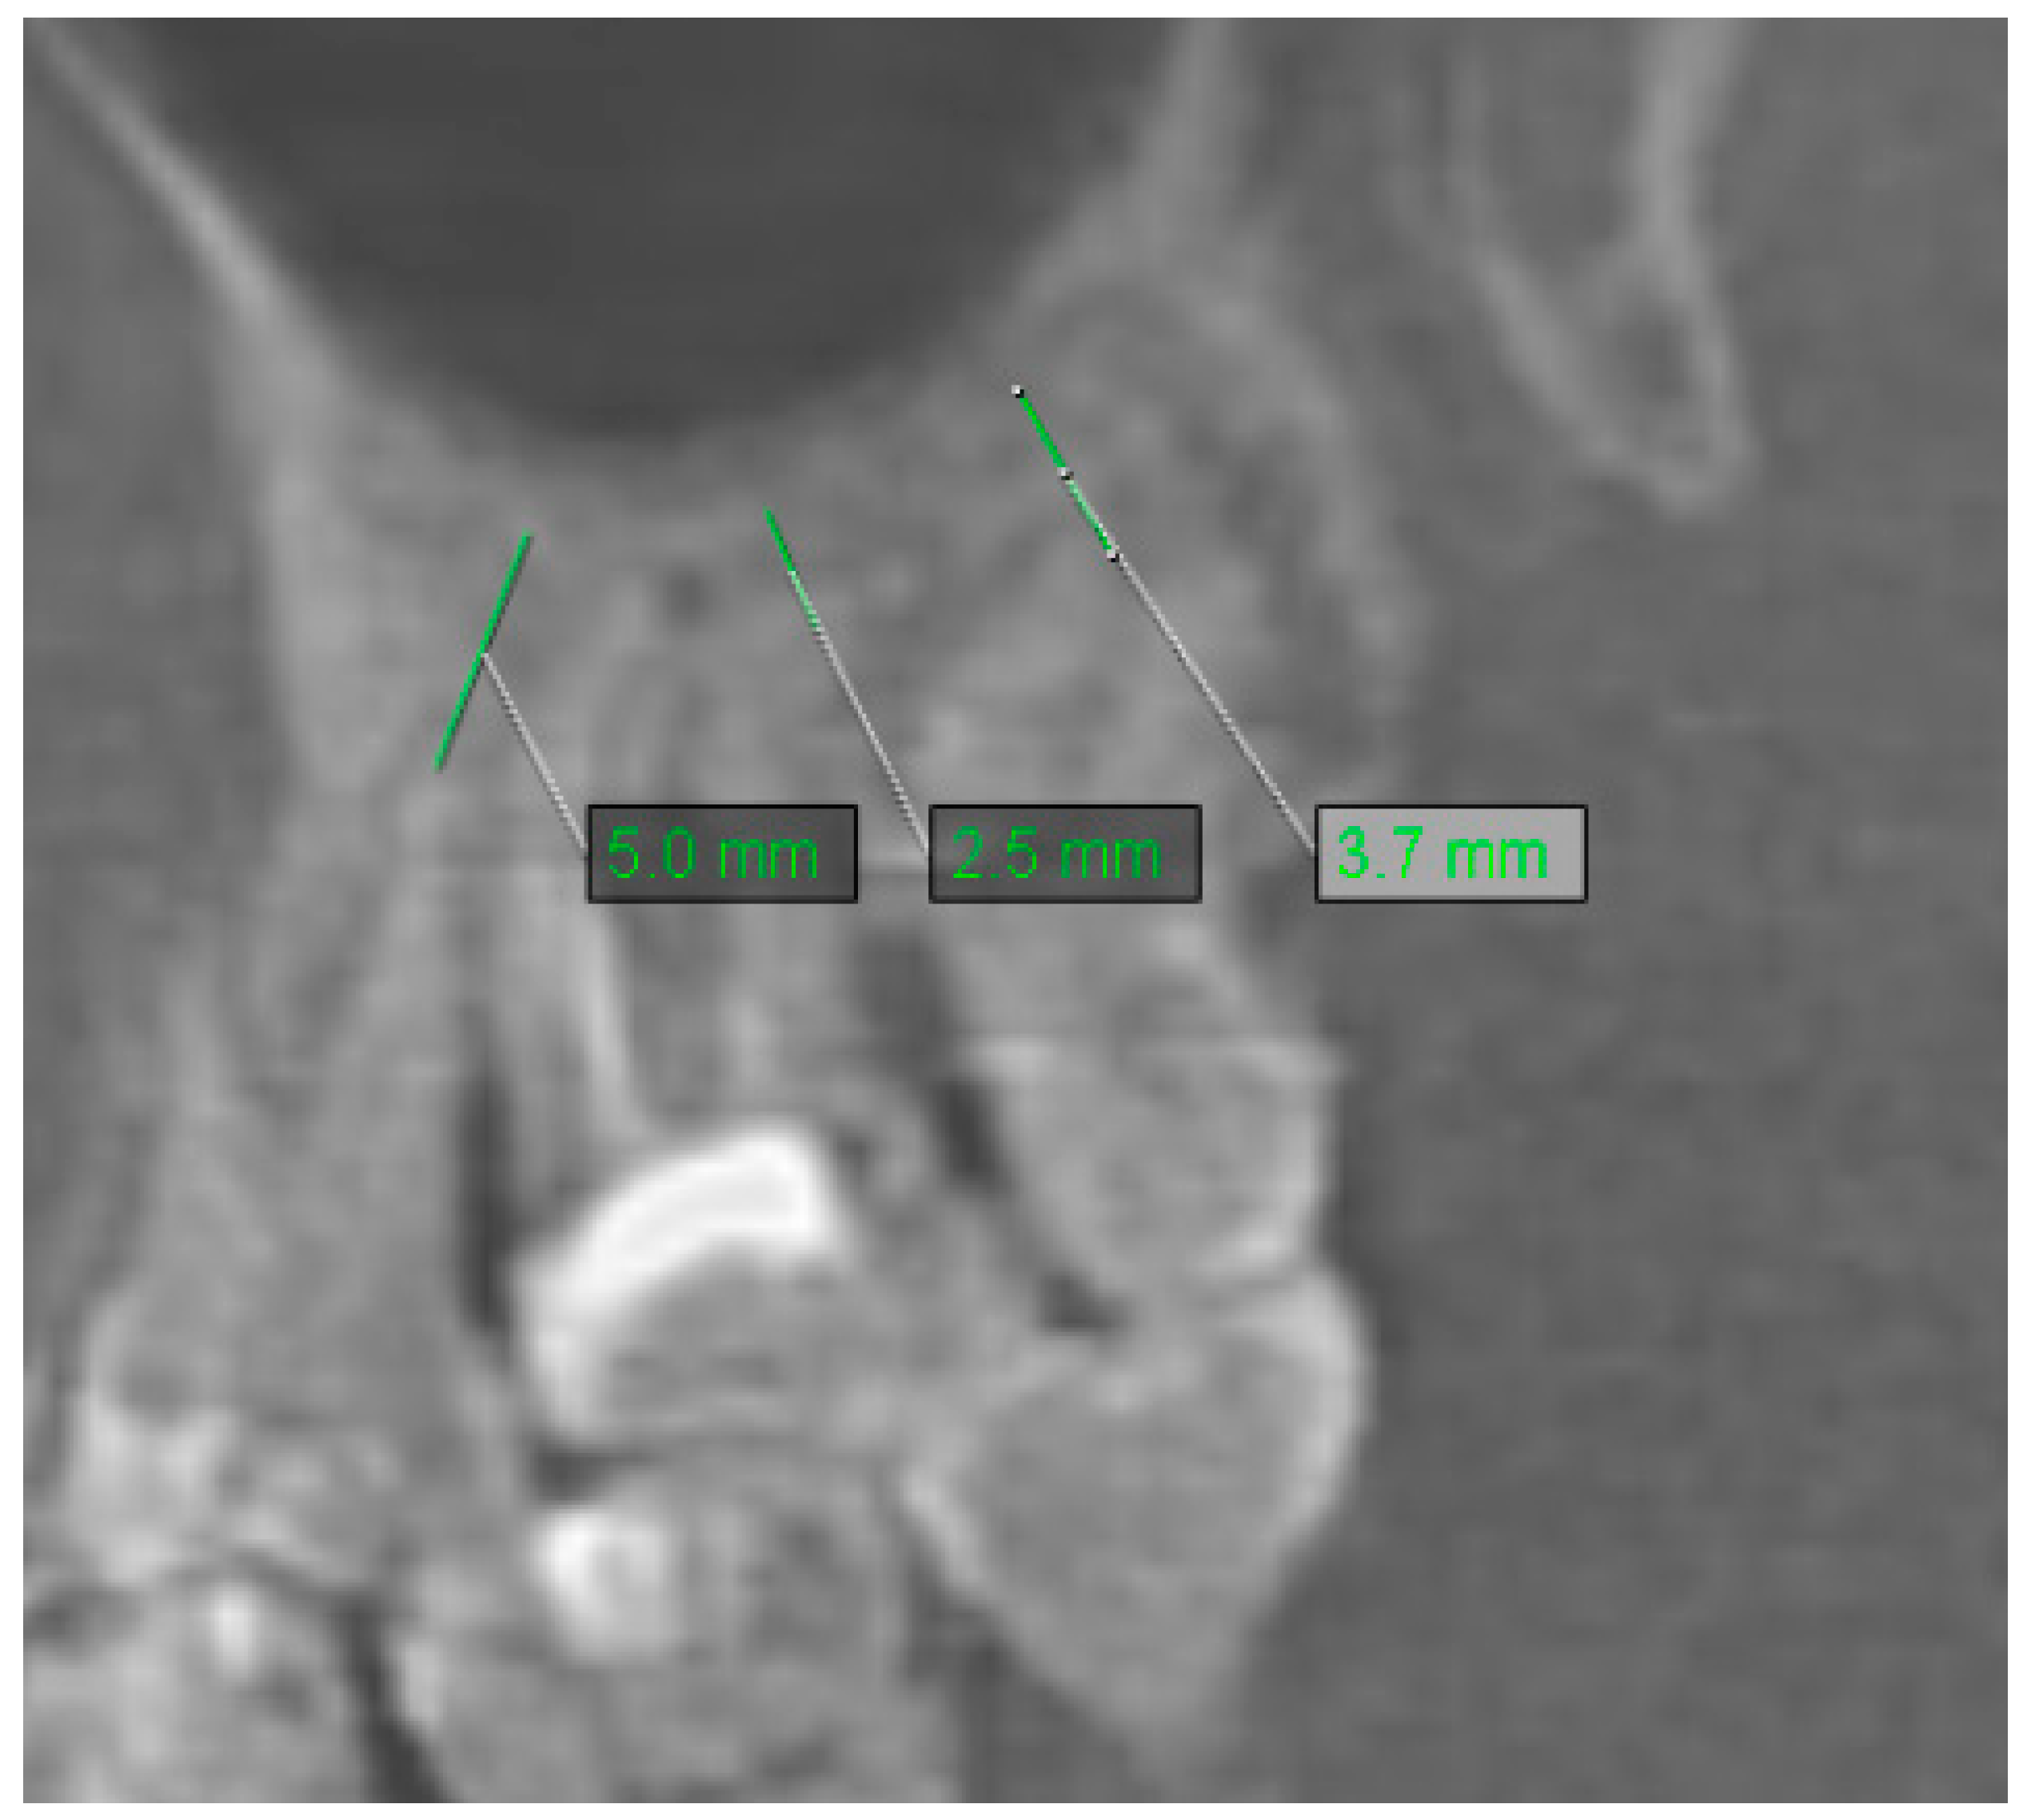

2.2. Assessment of Anatomic Relation between Teeth and Maxillary Sinus

2.3. Assessment of Periodontal Bone Loss